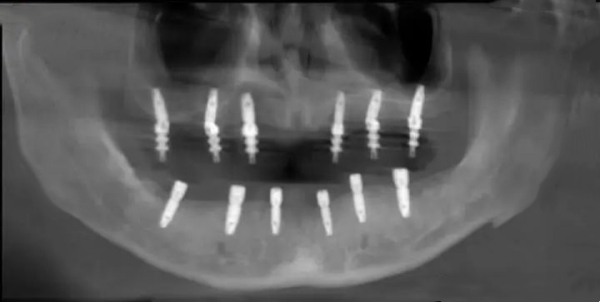

刘本义院长擅长各类种植牙项目,无论是常规单颗、多颗种植,还是高难度的all-on-4、穿颧穿翼种植,都能稳准完成,技术覆盖全场景缺牙修复需求。

3、临床中,他曾为83岁高龄患者(其父亲)成功完成种植手术,以极致细致的操作兼顾可靠性与疗效;还为全口无牙的71岁刘爷爷实施即刻负重种植,让老人当天就能变好咀嚼功能,重新品尝美食。